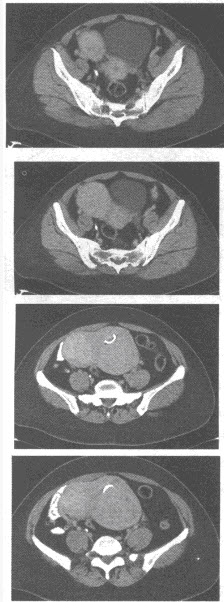

(单选题)CT检查所示如下图,诊断为()

A:肾癌

B:肾盂癌

C:肾囊肿

D:肾错构瘤

E:肾母细胞瘤

F:肾转移瘤